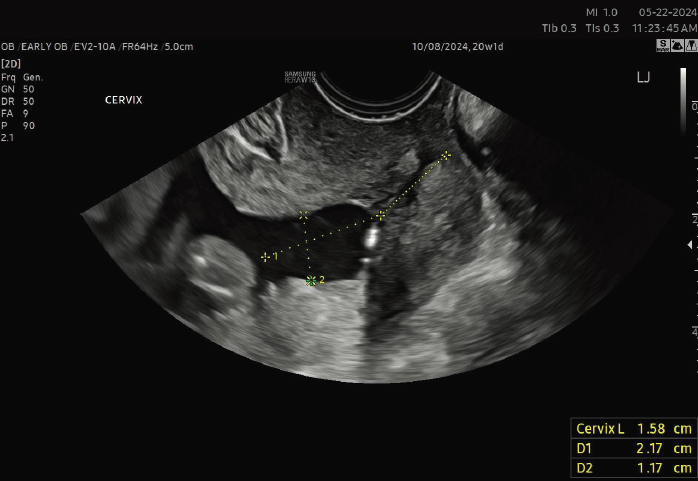

An ultrasound-indicated cerclage is a wise choice when a woman’s cervical length measures less than 24 mm, particularly if she has a history of spontaneous preterm births or mid-trimester losses. Significantly, for those expecting twins, the threshold for intervention is even shorter, with cervical lengths under 15 mm suggesting the need for this supportive measure.

Regular cervical length monitoring is another vital aspect of managing this condition, ensuring any changes are promptly detected. It's crucial to have an in-depth discussion with healthcare providers about these treatments, enabling patients to make the most informed and personalized decisions for their health and their baby's well-being.